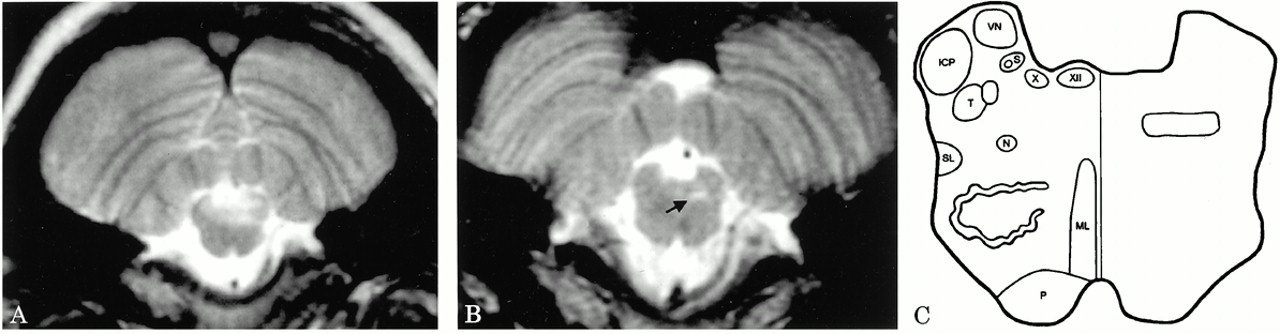

一个23岁的女人面对10天的进步麻木的脸和手臂,复视,振动幻视,吞咽困难。她不能打喷嚏或打哈欠,吃饭之后5分钟的问题。她有静脉血栓形成史和家族史的系统性红斑狼疮(SLE)。一般检查是非凡的颧骨皮疹。神经系统检查有乐观的眼球震颤,但眼睛运动的正常范围。左面部感觉减少。面部运动和听力都是正常的。腭感觉完整,但是运动是缺席。咳嗽、吞咽,舌头运动受损。触摸和销感觉减少武器但是没有其他long-tract迹象。 MRI revealed evidence of extensive brainstem demyelination, but no other abnormalities (图)。系统性红斑狼疮的诊断是由积极的安娜和anti-Ro抗体。CSF非细胞;寡克隆乐队没有礼物。她对待四甲基强的松龙,紧随其后的是口服强的松。八个月后她唯一症状是持久不能打喷嚏。鼻过敏导致的强烈欲望打喷嚏,她能主动模仿打喷嚏,但没有缓解症状。否则考试是正常的。重复MRI(参见图)演示了一个小型剩余异常延髓吻背外侧,“打喷嚏中心”的预测。1、2

图。(一)t2加权MRI在初始演示展示了一个广泛的脑干低信号异常与髓鞘脱失一致。后续图像8个月后(B)显示了一个小型残余面积增加T2信号只在“打喷嚏中心”(箭头所指)。根据解剖图像显示,而不是放射,公约(背方面的)。(C)图演示了病变的位置在“打喷嚏中心”在延髓吻背外侧(右)和主要的脑干核和大片的近似位置(左)。ICP =小脑下脚,毫升=内侧丘系,N =核ambiguus, P =金字塔,S =孤束核和呼吸道,SL =脊髓丘系,T =三叉神经束和核(相邻),VN =前庭神经核,X =迷走神经背核,十二=舌下神经核。